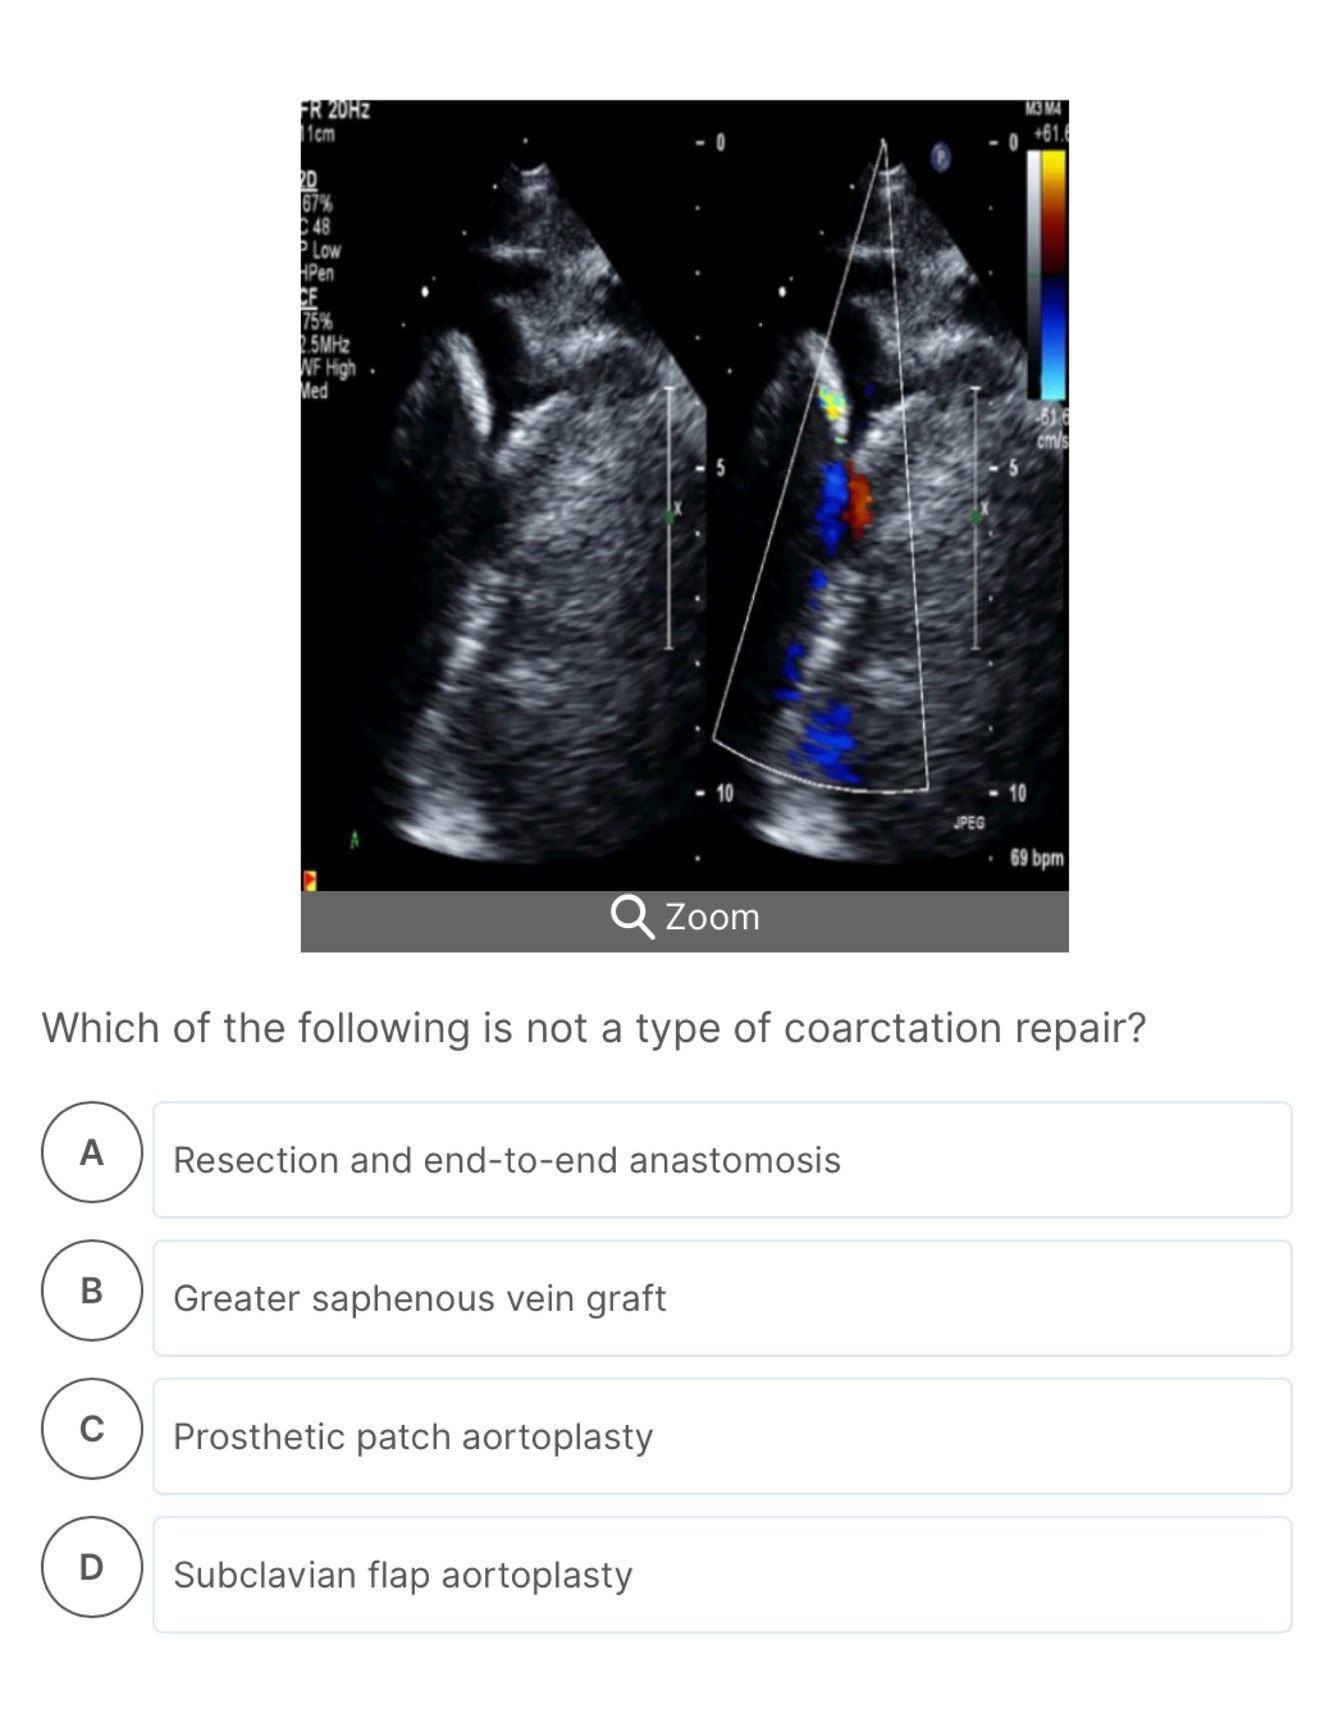

30